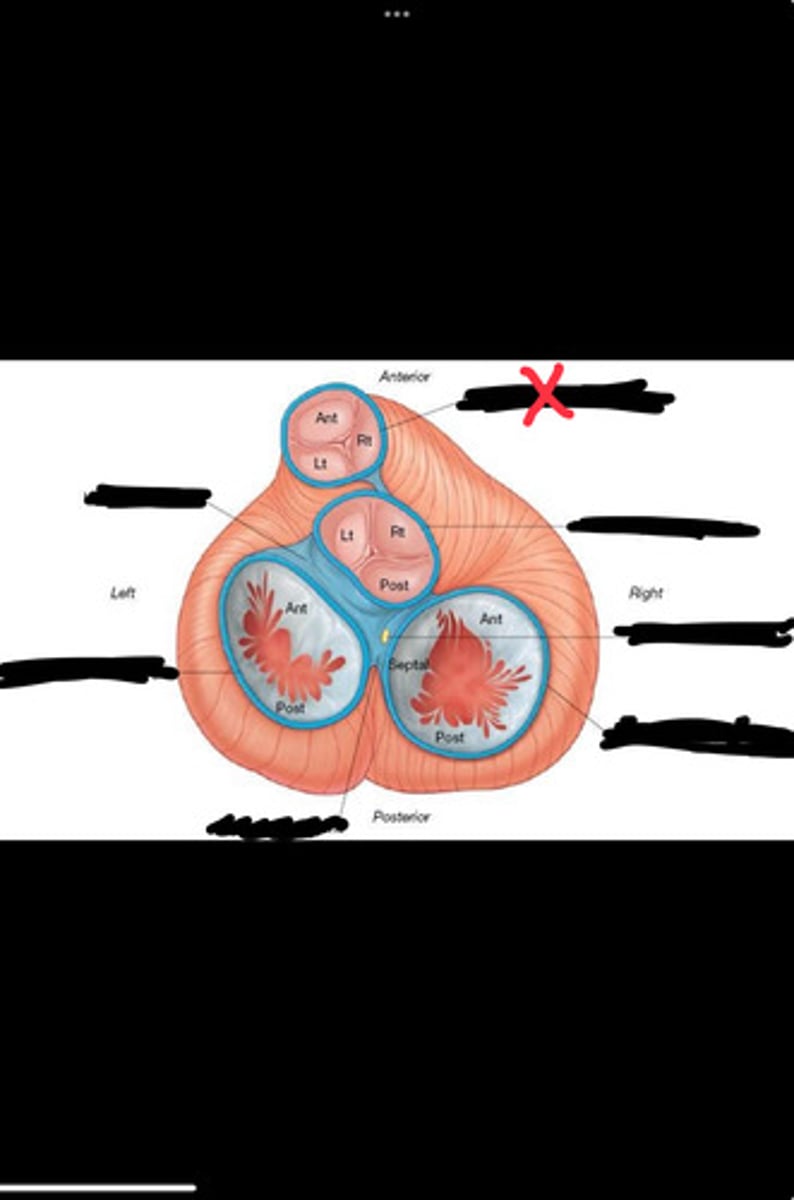

Right fibrous trigone

Left fibrous trigone

Fibrous ring of pulmonary valve

Fibrous ring of aortic valve

Atrioventricular bundle

Right atrioventricular ring

Left atrioventricular ring